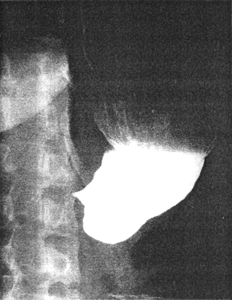

Case 39.1 L.M., female aged 29 years, accidentally swallowed a cupful of hydrochloric acid. This was followed by burning restrosternal and epigastric pain and continuous vomiting. Radiographic examination a week later revealed no abnormality in the oesophagus. A severe stricture, causing almost total occlusion of the lumen and commencing as a funnel-shaped narrowing in the region of the incisura angularis, was seen in the distal third of the stomach (Fig 39.1). At times a trickle of barium traversed the stricture, which was constant; the sphincteric cylinder and pyloric aperture were unidentifiable, with total absence of cyclical contraction and relaxation. Repeat examination after another week showed similar features, although the stricture appeared to be somewhat less severe. Antrectomy and Billroth I anastomosis 3 weeks after the incident showed the distal 5.0 to 6.0cm of the stomach to be oedematous and stenotic; the duodenum appeared normal. Microscopically severe fibrotic change was seen in the submucosa, with areas of necrosis and partial regeneration in the mucosa.

| Fig. 39.1. Case L.M. Funnel-shaped, severe stricture in distal stomach |